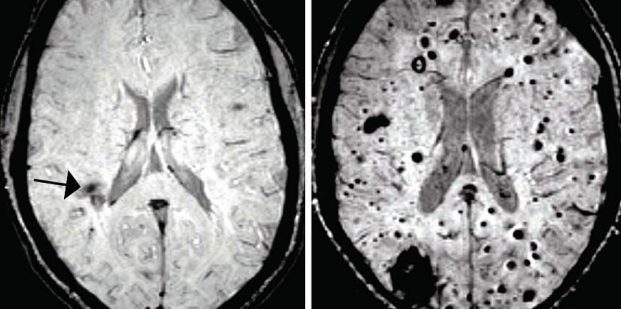

ناهنجاری های مغزی کاورنوس یا غار مانند (CCMs) دسته هایی از عروق خونی منبسط شده با دیواره های نازک شده هستند که میتوانند در هنگام نشت خون به بافت مغزی اطراف، باعث تشنج یا سکته شوند. تیمی از دانشمندان در دانشگاه پنسیلوانیا مکانیزم هایی را مورد بررسی قرار دادند که باعث تولید ضایعه های CCM در مغز موش هایِ مهندسیِ ژنتیک شده، میشوند؛ و سپس ارتباط غیر منتظره ای آن را با یک باکتری موجود در شکم پیدا کردند. زمانی که باکتری از بین رفت، تعداد ضایعات مذکور به طور چشم گیری کاهش یافت.

حال سوال اینجا بود که حضور این باکتری ها در جریان خون، چگونه میتواند رفتار عروق خونی مغز را تحت تاثیر قرار دهد. باکتری گرم-منفی، مولکول هایی با نام (lipopolysaccharides (LPS تولید میکنند که پتانسیل بالایی در فعالسازی سیگنال های طبیعی سیستم ایمنی دارند. زمانی که به موش ها، فقط LPS تزریق شد، تعداد زیادی ضایعات CCM بزرگ در مغز آنها شکل گرفت؛ درست شبیه مواردی که در عفونت باکتریایی ایجاد شده بود. در مقابل، زمانی که گیرنده های LPS (با نام TLR4) به صورت ژنتیکی در موش ها حذف شدند، دیگر ضایعه ای در مغز آنها ایجاد نشد. محققین دریافتند که در انسان ها نیز، جهش های ژنتیکی ای که باعث افزایش بیان TLR4 میشوند، با افزایش ریسک شکل گیری CCMs در ارتباط هستند.

محققان، تغییرات باکتری های بدن (میکروبیوم) را با دو روش بررسی کردند. اول، موش های مدل CCM را در شرایط عادی یا شرایط بدون میکروب پرورش دادند. دوم، به این موش ها آنتی بیوتیک داده شد که میکروبیوم آنها مجددا تنظیم شود. در هر دو حالت، هم تزریق آنتی بیوتیک و هم شرایط بدون میکروب، تعداد ضایعه ها به طور قابل ملاحظه ای کاهش یافت که نشان میدهد دو عامل کمیت و کیفیت میکروبیوم شکم میتواند در شکل گیری CCM ها تاثیرگذار باشد. در نهایت، دارویی که گیرنده های TLR4 را مسدود میکند، به طور چشم گیری، تشکیل ضایعات را کاهش داد. این دارو برای درمان عفونت منتشر خونی (سپسیس) مورد تست بالینی قرار گرفته است و اکنون نیز پتانسیل اثر درمانی آن در CCMs مشاهده شده است. با این حال تحقیقات زیادی در این زمینه باید انجام شود.